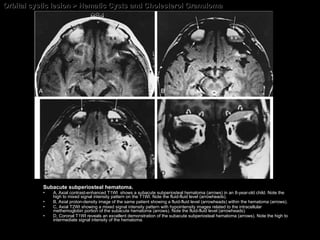

Hematic Cysts and Cholesterol Granuloma CT findings of Subperiosteal hematomas Acute hematoma  = sharply defined extraconal, homogeneous, high-density, nonenhancing mass with a  broad base abutting the bone and displacing the peripheral orbital fat .  Chronic hematoma  = sharply defined extraconal,  heterogeneous ,  relatively hypodense , nonenhancing mass.  Long-standing chronic hematic cysts  (cholesterol granulomas) = cystic lesions, associated with  compression bone atrophy  as well as expansion and erosions of adjacent bone.

Hematic Cysts and Cholesterol Granuloma MR findings of Subperiosteal hematomas

Orbital cystic lesion > Hematic Cysts and Cholesterol Granuloma Subacute subperiosteal hematoma.  A, Axial contrast-enhanced T1WI  shows a subacute subperiosteal hematoma (arrows) in an 8-year-old child. Note the high to mixed signal intensity pattern on the T1WI. Note the fluid-fluid level (arrowheads).  B, Axial proton-density image of the same patient showing a fluid-fluid level (arrowheads) within the hematoma (arrows). C, Axial T2WI showing a mixed signal intensity pattern with hypointensity images related to the intracellular methemoglobin portion of the subacute hematoma (arrows). Note the fluid-fluid level (arrowheads).  D, Coronal T1WI reveals an excellent demonstration of the subacute subperiosteal hematoma (arrows). Note the high to intermediate signal intensity of the hematoma.